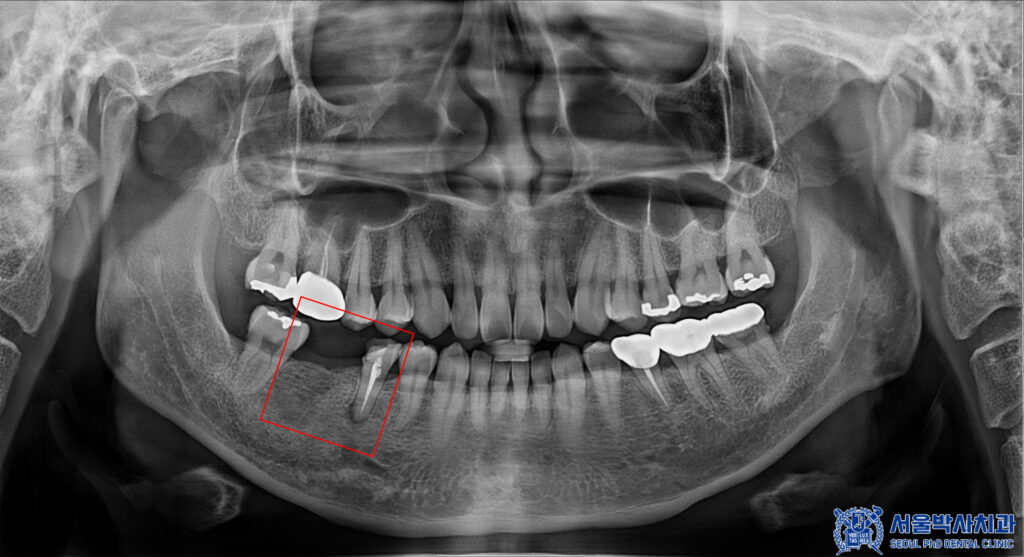

치아를 확인해 보니,

오른쪽 아래 작은 어금니는

이미 예전에 다른 곳에서

신경치료까지 받았던 부분이나

충치와 염증이 발생하였습니다.

그래서 해당 치아는 살려보고자

재신경치료를 진행하기로 하였습니다.